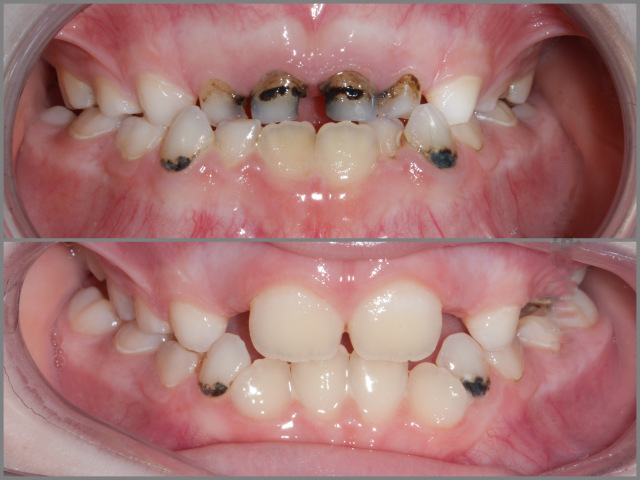

Скобы (Пластинки) для зубов: фото до и после